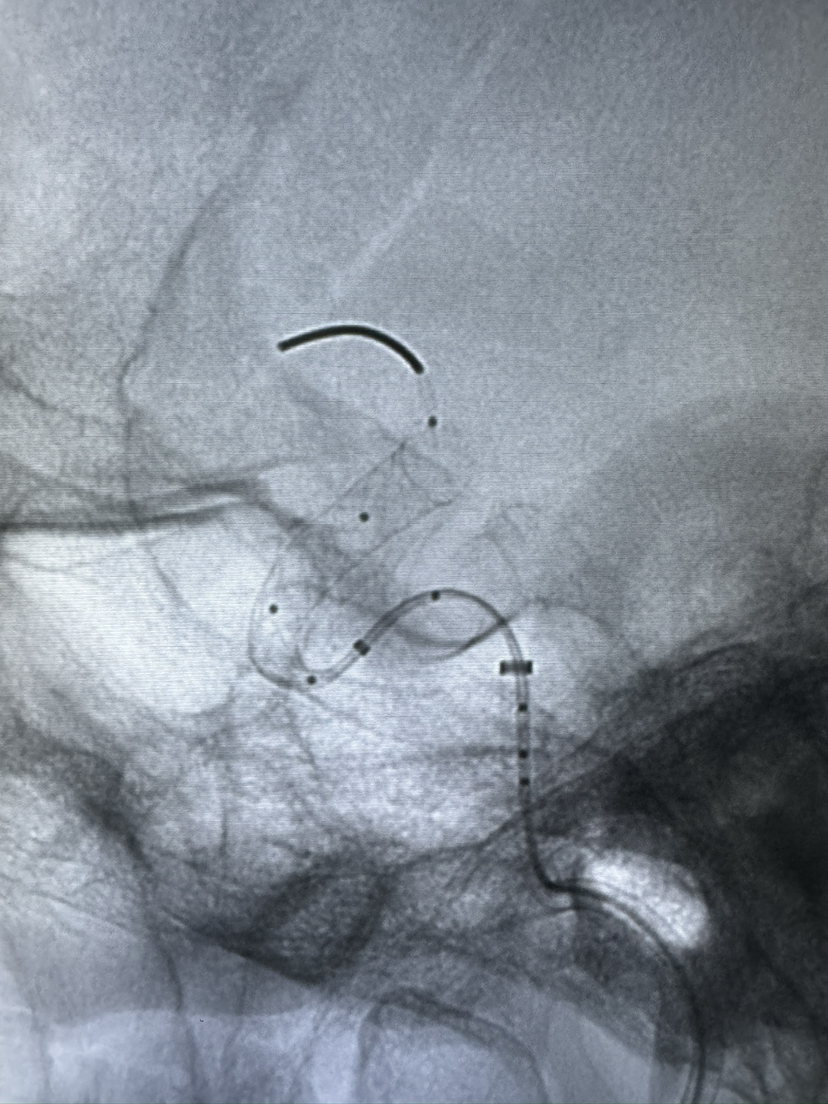

Lattice 支架治疗眼动脉动脉瘤,Scepter c 球囊后扩辅助海绵窦段支架打开